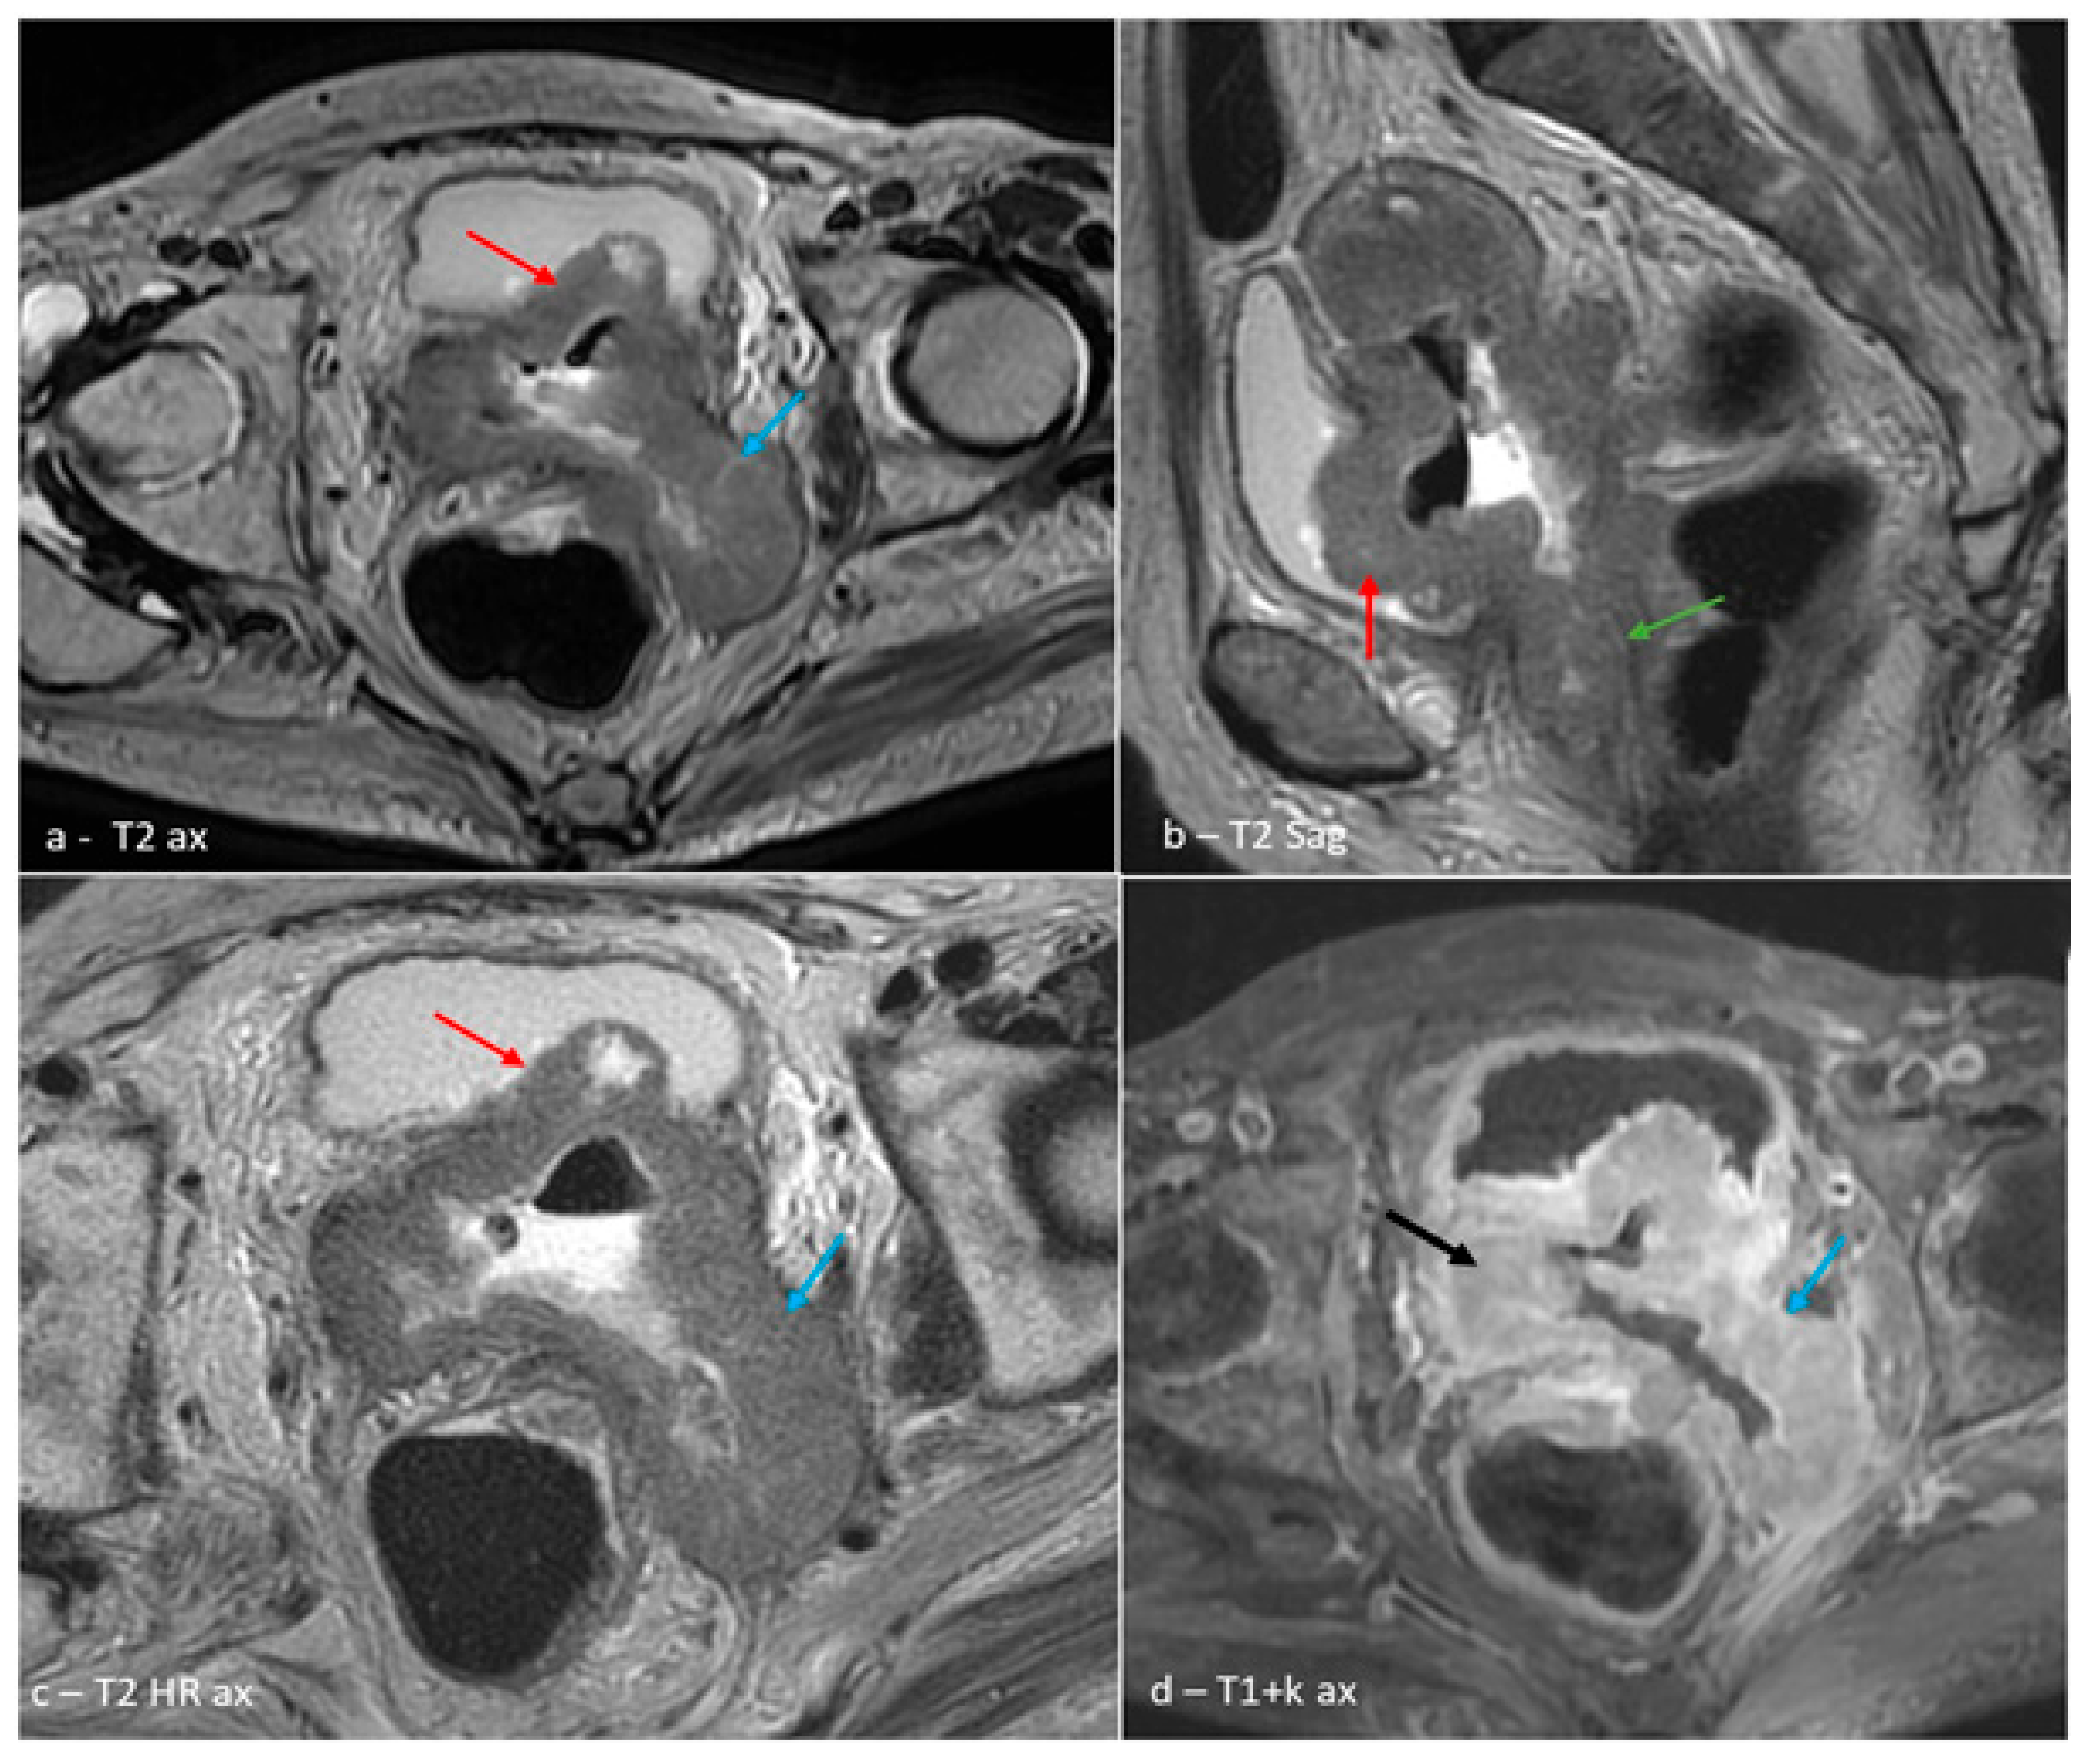

2. Case Presentation